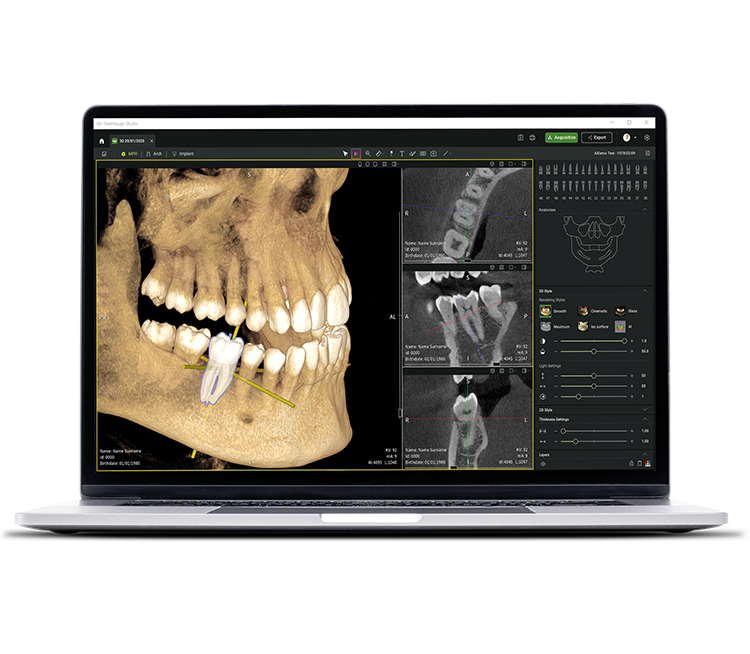

• Seethrough Studio

See tomorrow. See a new level.

En plus des technologies matérielles sophistiquées, le logiciel Seethrough Studio révolutionnaire est le facteur déterminant pour assurer le niveau de qualité élevé de l’ensemble de la gamme de solutions d’imagerie de W&H :avec des fonctions utiles et des algorithmes avancés, Seethrough Studio est une solution intégrale qui élève l’imagerie et les flux de travail en odontologie numérique à un niveau supérieur.

Outil de planification implantaire intégré

En plus d’une qualité d’image exceptionnelle et d’une utilisation intuitive, Seethrough Studio offre de

nombreuses fonctions utiles, comme un outil de planification d’implants intégré par défaut, pour simplifier la visualisation et la préparation du traitement.

Fonctions assistées par l'IA

Seethrough Studio a recours à différents outils d’IA pour améliorer encore davantage l’imagerie, par

exemple l’orientation des volumes 3D, la segmentation dentaire, le tracé des arcades, la détection automatique du canal mandibulaire

et une assistance précieuse pour la suggestion de pathologies.